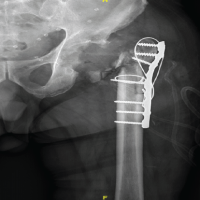

Hip X-ray shows no fracture, implant properly seated, and no evidence of loosening or osteomyelitis.

- He completed a total of 6-week course of Ceftriaxone 2 g 12 hourly (2 weeks as an inpatient and 4 weeks as an outpatient). The patient was reviewed at 6 weeks at outpatient clinic, with healthy suture line (Fig. 1) and all inflammatory markers were normal. His X-ray hip joint (Fig. 2) normal with retained implant. The clinical examination of hip was normal. There was no evidence of clinical, radiological, or microbiological treatment failure at follow-up. He came for follow-up at orthopedic outpatient department and the X-ray (Fig. 3) shows the X-ray hip joint with no evidence of bony involvement, no lysis or periosteal reaction suggestive of osteomyelitis and hip joint can bear weight normally (Fig. 4). He will be followed up at 8 months and 12 months to ensure no relapse.